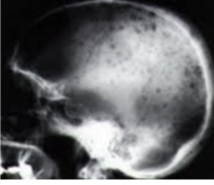

안타깝게도 다발골수종의 정확한 발병 원인이 알려지지 않아, 예방법은 없다. 다만, 무증상 단계에서 건강검진 시 M단백이 발견되는 경우가 있는데, 일찍만 발견하면 치료 예후가 훨씬 좋은 만큼 정기적인 건강검진이 악화를 막는 최선의 예방책이 될 수 있다. 혈액·소변 검사에서 M단백이 발견되면 골수검사 등 추가 검사들을 통해 다발골수종으로 확진하고, 전신 CT(컴퓨터단층촬영)나 MRI(자기공명영상) 등 검사로 골 침범 병변이 있는지 등을 확인하게 된다.

병이 진행하는 동안 환자들은 고칼슘혈증으로 인한 졸음, 의식 저하, 오심, 구토 등 위장관 증상, 빈혈과 콩팥 기능 저하로 인한 피로, 숨찬 증상, 부종, 골 병변으로 인한 허리, 관절 통증, 압박골절, 하지마비 등 신경학적 증상 등을 겪는다. 환자의 70% 정도에선 뼈 통증, 골절 등 정형외과적 문제로 병원을 방문했다가 다발골수종으로 진단받고, 환자의 20% 정도는 콩팥 기능 저하, 빈혈 등으로 병원을 찾는다.